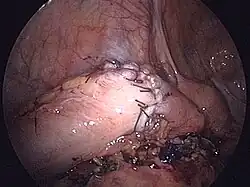

- Przykład zespolenia maszynowego i ręcznego

Zespolenie maszynowe (resekcja esicy). Połączenie grzybka i aparatu z kikuta. Zbliżanie i przygotowanie do zespolenia.- Ręczne zespolenie jelita. Pod jelitem widoczne plastikowe klipsy dla zaopatrzenia naczyń (niebieskie).

Zaopatrzenie naczyń przy pomocy wchłanialnych klipsów.